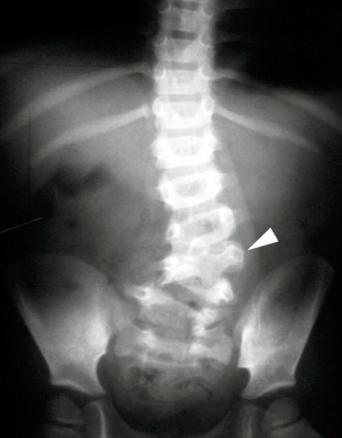

Radiographie du rachis lombaire de face montrant une scoliose par anomalie congénitale (hémivertèbre lombaire).